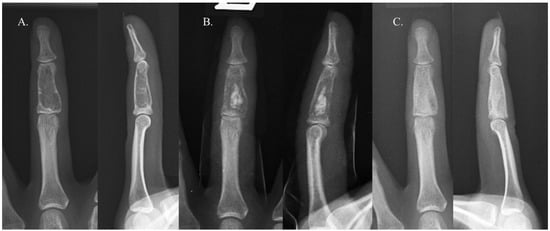

Recurrence occurred in only one case. The patient in question was a 22-year-old woman with an enchondroma in the middle phalanx of her left third finger. She underwent curettage and allogenic cancellous chip bone grafting. The bone graft filled approximately 39% of the defect, categorizing it as Group B (Figure 2). Sixteen years later, the enchondroma recurred in the same location. Repeated curettage and allogenic cancellous chip bone grafting were performed, and pathological analysis confirmed the presence of an enchondroma (Figure 3). There were no complications, such as infection, malunion, persistent pain, or refracture, in either group.

Figure 3. Simple radiographs of a patient with recurrence 6 years (A), immediately after surgery (B), and 1 year after surgery (C).